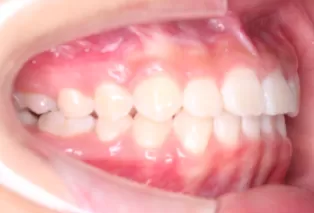

Intraoral photos